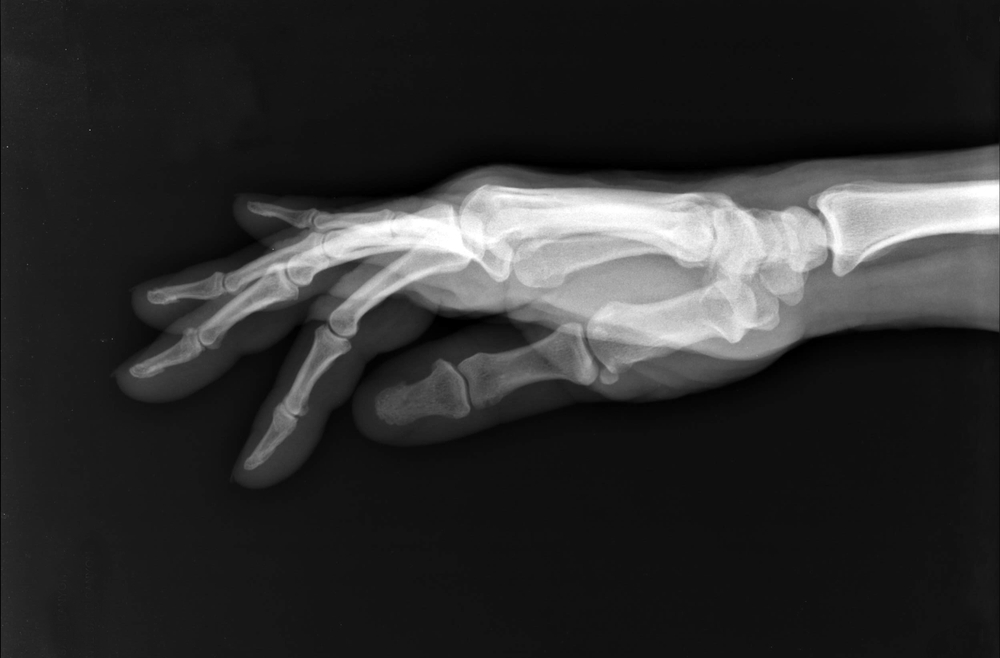

An x-ray may show deterioration of the joint as well as any bone spurs or calcium deposits that have developed.